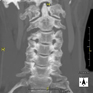

Prueba radiológica que consiste en obtener imágenes de las vertebras cervicales de alta definición anatómica mediante el empleo de un equipo de TC (Tomografía Computarizada). Indicaciones: cervicalgia sin/con irradiación a brazos, traumatismo.

Prova radiològica que consisteix en obtenir imatges de les vèrtebres cervicals d'alta definició anatòmica, mitjançant l'ús d'un equip de TC (Tomografia Computeritzada). Indicacions: dolor cervical amb/sense irradiació als braços, traumatisme, malformacions congènites. - TC Columna dorsal